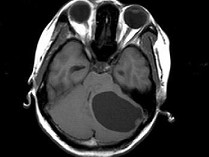

女,27岁,头昏、行走不稳1个月,PE:指鼻试验(+),Romberg氏征(+),根据所提供图像,最可能的诊断()

A.左小脑脓肿

B.左小脑血管母细胞瘤

C.左小脑星形细胞瘤

D.左小脑胶质细胞瘤

E.左小脑转移瘤

女,27岁,头昏、行走不稳1个月,PE:指鼻试验(+),Romberg氏征(+)

[单选题]女,27岁,头昏、行走不稳1个月,PE:指鼻试验(+),Romberg氏征(+),根据所提供图像,最可能的诊断()A . 左小脑脓肿B . 左小脑血管母细胞瘤C . 左小脑星形细胞瘤D . 左小脑胶质细胞瘤E . 左小脑转移瘤